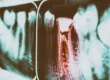

Il problema è che ci sono patologie che hanno un esordio asintomatico, come la carie, che per anni potrebbe scavare indisturbata nel tuo dente senza che tu te ne accorga, per poi arrivare al punto di provocarti forti dolori.

Prendiamo proprio la carie come esempio pratico: quando si trova agli esordi, generalmente asintomatica, il suo trattamento consiste in una semplice otturazione, con costo decisamente accessibile alla maggior parte delle persone.

Ma se decidi di ignorarla, sarà in grado di raggiungere il nervo, con la necessità di ricorrere alla devitalizzazione, perché la polpa dentale ormai risulta danneggiata; nei casi peggiori, si dovranno considerare persino degli impianti per sostituire il dente ormai irrecuperabile, con conseguente incremento delle spese di intervento.